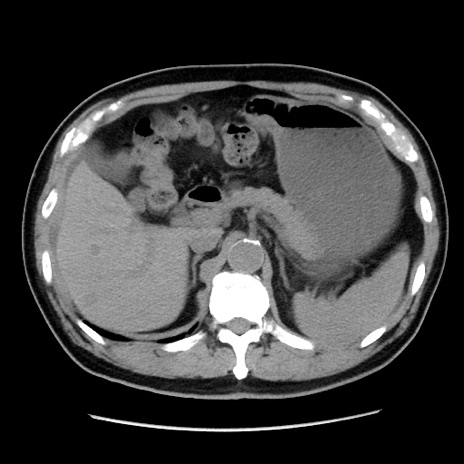

冠状断像